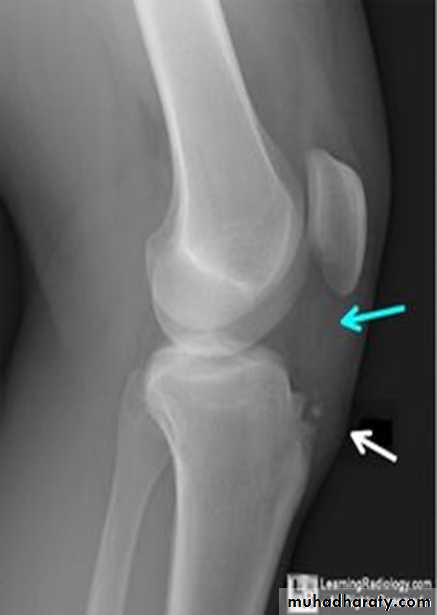

Osgood-Schlatter disease.

Fragmentation of the tibial tuberosity

Osgood-Schlatter : 12-16 y,osteochodrosis of the tibial tuberocle.